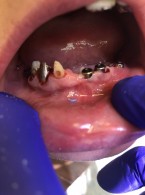

Kandydoza jamy ustnej – jak ją rozpoznać i prawidłowo leczyć?

Zobacz więcej

12.50PLN